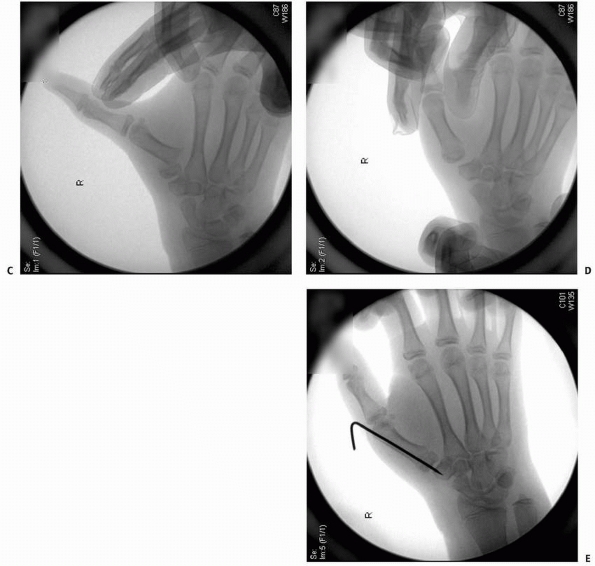

![]() |

FIGURE 8-32 A. A 10-year-old girl with a displaced unicondylar fracture of the ring finger proximal phalanx. B. Clinical examination reveals malrotation of the digit. C. Dorsal exposure with incision between lateral band and central slip. D. Exposure of displaced fracture fragment. (continues)

FIGURE 8-32 (continued) E. Fracture reduced with Kirschner-wire fixation. F.